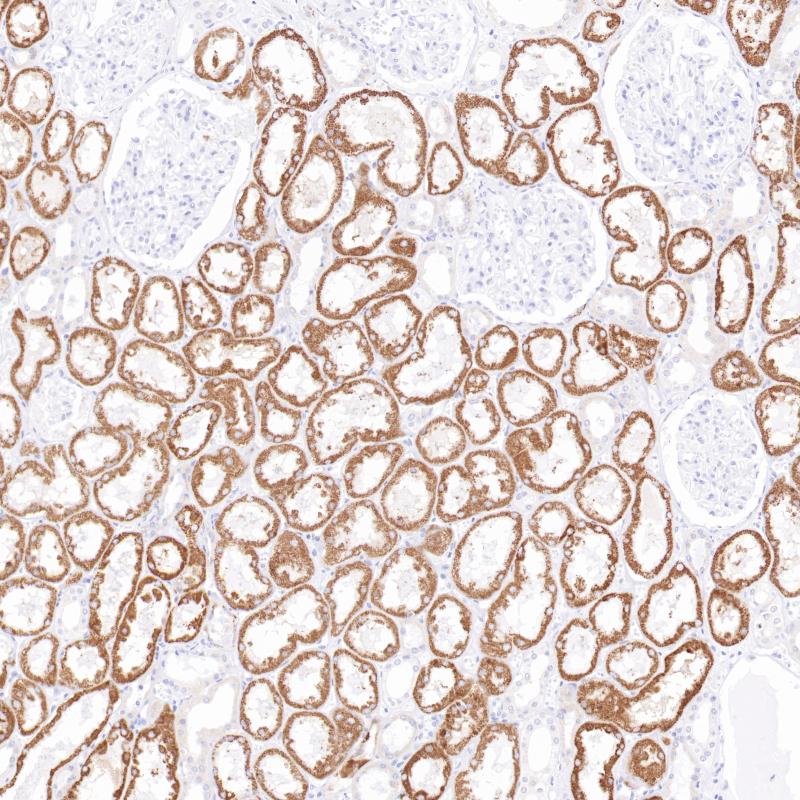

肾AMACR(BPM6227)染色

AMACR (P504S蛋白)在支链脂肪酸及其衍生物的β -氧化中起作用。AMACR存在于前列腺、肝、胆道、肾、肺等多种组织的线粒体和过氧化物酶体中。在90%以上的前列腺癌中发现了AMACR的弥漫染色模式。AMACR抗体主要用于前列腺癌的临床诊断。